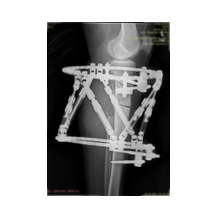

Deformitenin yeri ve miktarına bağlı olarak bilgisayar destekli sirküler eksternal fiksatör ile tedrici düzeltme yapılabilir. Bu sistemin avantajı düzeltme esnasında sistemle oynayarak yeni düzenlemeler yapmanıza izin vermesidir.

Bu ameliyat öncesi bir deformite analizi yapılıp hangi kemikte, normalden ne kadar sapma olduğu tespit edilir. Daha sonra bu kemiğe yine ostetomi yapılarak bu anormal sapma düzeltilir.  Bu düzeltme plak-vida veya intramedüller çivi ile akut olarak düzeltilebileceği gibi bilgisayar destekli sirküler eksternal fiksatör ile tedrici olarak ta yapılabilir. Hangi yöntemin hangi hasta için uygun olacağına hasta özelinde karar veriyoruz, ne tür cerrahi tedavi olması gerektiğini danışabilirsiniz.